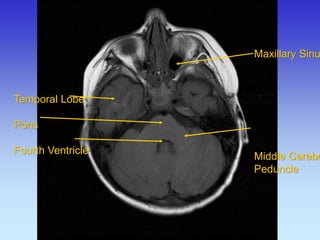

Temporal Lobe

Pons

Fourth Ventricle

Maxillary Sinus Middle Cerebellar Peduncle